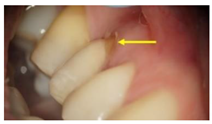

GroupDescription Clinical Presentation

Group-III (n = 30)Received zirconia-based prostheses fabricated by the CAD/CAM technique. Zirconia was milled using the CAD/CAM system from pre-sintered zirconia blocks, sintered, and followed by porcelain layering.Molecules 26 01331 i003

Arrows show the crown margins and gingival tissues interface.